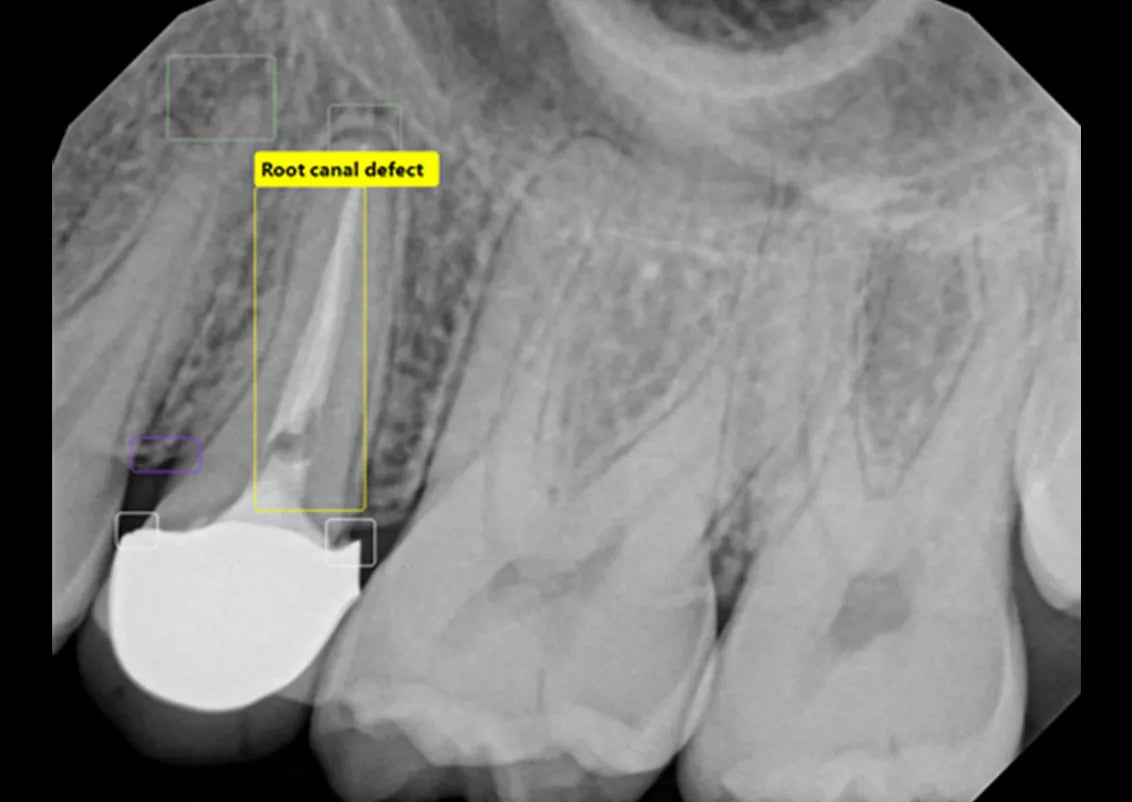

Built into DEXIS™ Imaging Suite Software, the DEXassist Solution provides assisted intelligence with a single click. This new solution enables users to identify up to six dental findings on 2D x-ray images.